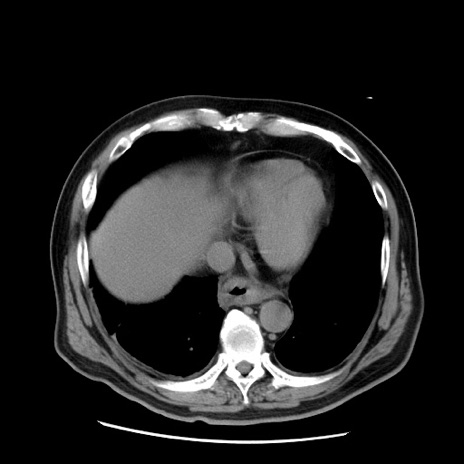

症例20(横断像)

【症例】 60歳代男性

【主訴】 腹部膨満、嘔吐

【現病歴】5日前頃より倦怠感を認め食事量減少し4日前の朝嘔吐、食事摂取困難となった。 3日前近医受診し点滴施行され整腸剤などを処方された。 当日他院を受診し、腹部膨満著明、炎症反応の上昇(CRP10.8、WBC11200)あり、紹介受診となる。

【身体所見】 意識JCS1 受け答えがはっきりしないBP 111/57mHg、 P 67bpm、、BT35.2°C、SpO2 97%(RA)、 腹部:膨隆、打診で鼓音あり、全体的に圧痛有り、腸蠕動音(-)、反跳痛ははっきりせず。

【データ】WBC 11400、CRP 14.20